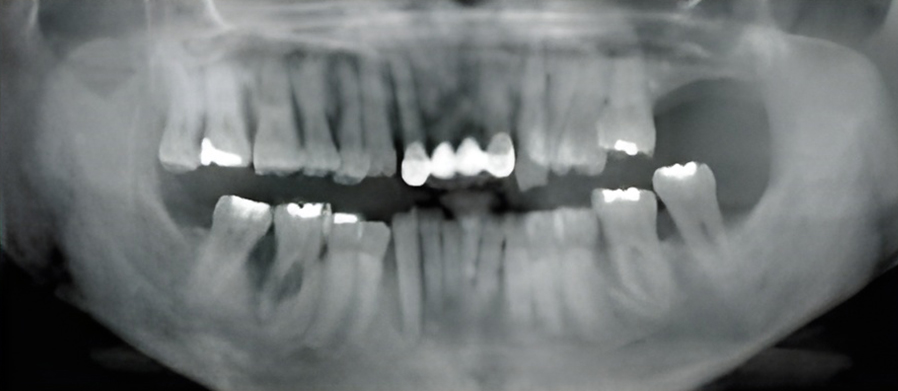

칫솔질과 치실질을 통해 매일 플라그를 제거하지 않으면 박테리아로 인해 잇몸 조직이 붉어지고 부어오르게 됩니다. 염증이 더 심해지면, 치아 주위 조직에 염증이 생기는 치주염으로 진행될 수 있습니다.

치은염을 치료하지 않고 방치하면 플라그가 뿌리로 퍼져 뼈와 연조직에 감염과 손상을 일으킬 수 있습니다. 잇몸이 치아에서 분리되어 물러나기 시작할 수 있으며 잇몸 라인 아래에 주머니가 생겨 플라크와 음식물이 쌓일 수 있습니다.

치주염은 스케일링을 통해 플라그와 치석을 제거하여 치료합니다. 문제가 되는 치주낭 부분을 제거하여 건강한 조직이 치아에 붙을 수 있도록 합니다.